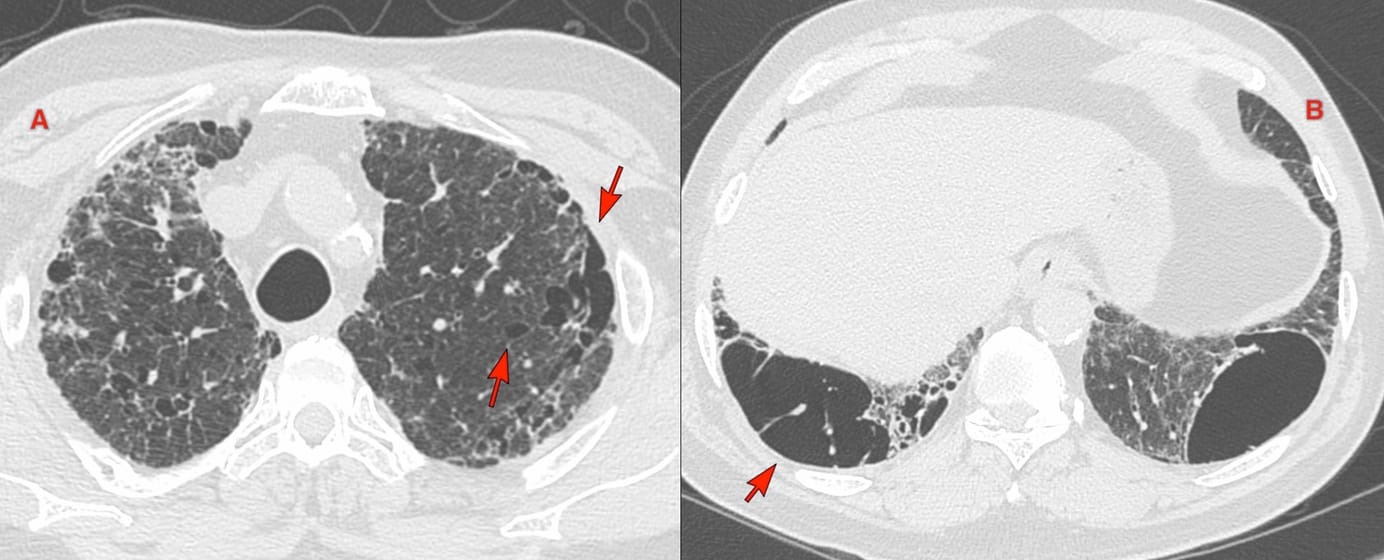

64-years old with rheumatoid arthritis on treatment had dyspnea. He was a 15-pack years smoker who had stopped 10 years ago. He was known to have ILD since 2023 and was on anti-fibrotics.